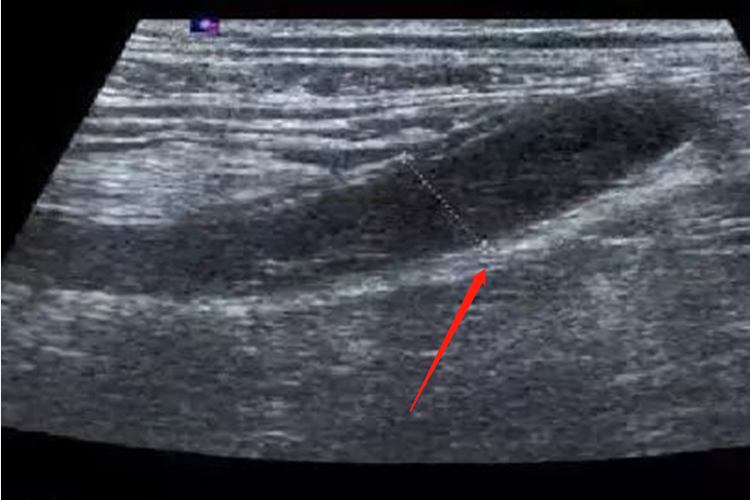

阑尾炎患者超声检查可发现肿大的阑尾或脓肿,而CT敏感性优于超声,治疗方式为手术。

影像学检查一般包括腹部平片、超声和CT,阑尾炎患者进行影像学检查时,腹部平片可见盲肠扩张和液气平面,偶尔可见钙化的肠石和异物影,可帮助诊断。超声检查可发现肿大的阑尾或脓肿。CT的敏感性优于超声,尤其有助于阑尾周围脓肿的诊断。此外,阑尾炎的患者还可能会出现腹痛、厌食、呕吐、乏力等症状。